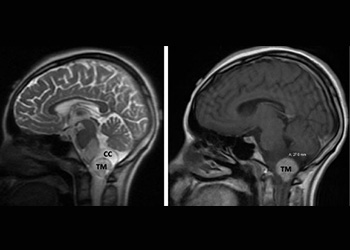

Endovascular:

Hydrocephalus and Brainstem Tumor

Author: Jonathan L. Brisman M.D., F.A.C.S., Read More!